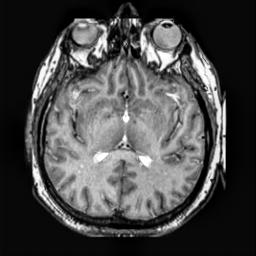

To demonstrate the effectiveness and efficiency of the proposed image fusion method , we conduct a set of comparative experiments on three image datasets. The first is composed by 8 pairs of multi-modal medical images and the second one contains 15 pairs of multi-focus gray or color natural images. These two datasets are often used in many related papers and some examples are shown in Figure 3(a) and Figure 3(b). The third one is a new multi-focus cervical cell image dataset collected by ourselves, which consists of 15 groups of color images and each group contains a series of multi-focus cervix cell images with size of or , etc. Some source examples are shown in Figure 3(c). Our source code implemented in C++ along with the new multi-focus cervical cell image dataset is available online.

We first evaluate the performance of the proposed method under varying total number of octaves and number of layers sampled per octave. The fused images of a pair of multi-modal medical images with different and are shown in Figure 4. In this example, on the one hand, when only 1 or 2 octaves are involved in constructing the DoG pyramid, the fused images fail to keep the integrity information of large size objects (e.g. eyeballs), while by increasing the value of , the integrity information of eyeballs is preserved. On the other hand, although not as significant as the increase of octave numbers , the fused image can contain more details by the increase of layer numbers . The corresponding objective quality metrics are shown in Figure 5. As shown in Figure 5(a), most of the metric values are improved as the number of octaves increases with the fixed layer numbers 3 in the global tendency and each of them tends to be stable when the number of octaves is 5. To get a relatively good quality from Figure 5(b), we can notice that some of the metric values can get a good performance when the number of layers is 3, such as the MI, SSIM, QI and VIF, though there are only a little change of all the metric values by increasing the number of layers with the fixed octave numbers 5. Because it will result in more computation burden with the increase of the value and , and for different kinds of source images, there are different performance with the diverse parameter settings. To get a trade-off between them in our experiments, we set for the multi-modal dataset, for the natural datasets and for the multi-focus cell dataset, respectively.

Figure 6 shows the fused images obtained by different methods with the multi-modal source images shown in Figure 3(a). As shown in these figures, the proposed method can produce images which preserve the complementary information of different source images well. Moreover, due to the scale-invariant structure saliency selection, our method can keep the integrity information of large size objects and the visual details simultaneously. Although the fused image generated by other methods can also capture the details to some extent, all of them fail to keep the integrity information of large size objects such as the eyeballs. Furthermore, from Figure 6(k)-6(t), the DTCWT, GFF, IM and NSCT methods may decrease the brightness and contrast while the proposed method can preserve these features and details without producing visible artifacts and brightness distortions.